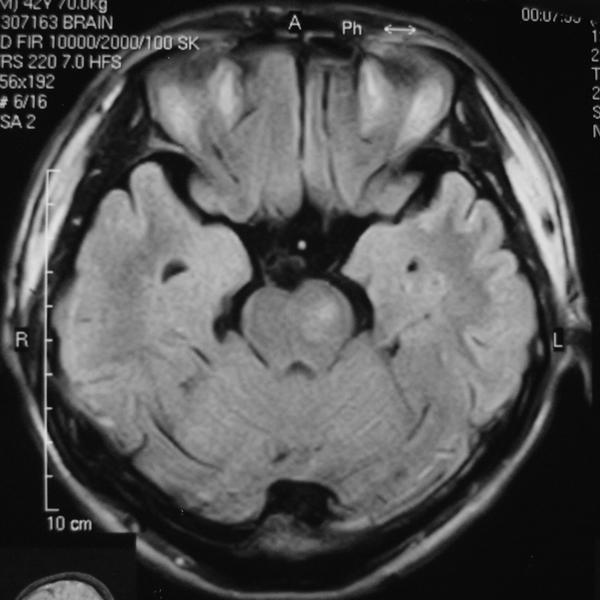

男 49岁 脑干腔隙梗塞5年。

这患者脑干(脑桥)腔隙脑梗塞是肯定的 有20002年资料 明天上传全部资料(当时工作忙 来不及)

1 单纯此图像定脑干梗塞依据不足. 2 可薄扫或核磁检查.

诊断依据不足,建议磁共振检查,

做磁共振吧!

脑干中脑区的梗塞还是能诊断的,建议薄扫一下。或者mri检查

脑干梗塞在ct上是斑点状低密度,一般只能在桥脑或中脑才能显示,延髓是很难发现(伪影多)。mr上脑干梗塞应该是长t1长t2的斑点状表现。弥散能够发现早期梗塞灶,表现高信号。

而小脑脚有三部分:①小脑下脚(绳状体)由脊髓小脑束组成, ②小脑中脚(脑桥臂)由脑桥小脑束组成, ③小脚上脚(结合臂)由出小脑纤维组成。小脑脚是正常神经纤维束构成,所以ct上密度是正常的(因为ct尚不能分辨脑干的细小神经纤维束);mr上是与正常白质一样的信号,而不是长t1长t2信号。

mri的优势